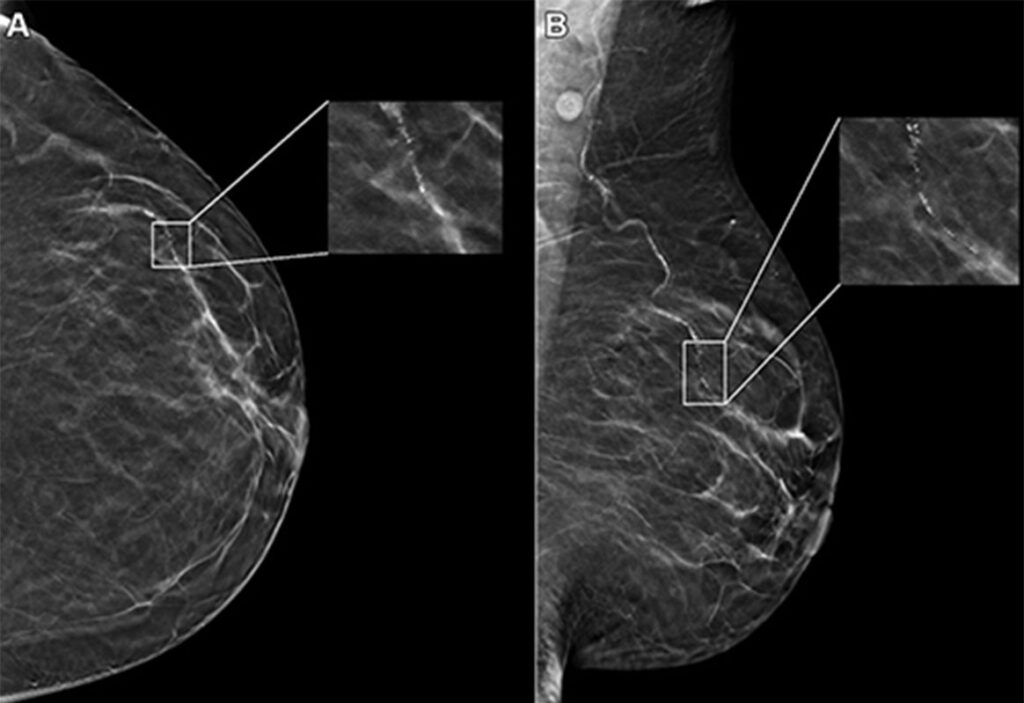

- Detection of Clinically Relevant Cancers: Transpara-supported screening led to increased detection of small, lymph-node negative, invasive cancers, and high-grade in situ cancers, which is crucial for early intervention and treatment.

The most clinically validated Breast AI on the market, Transpara provides radiologists with a ‘second pair’ of eyes to help detect cancers earlier and reduce recall rates.